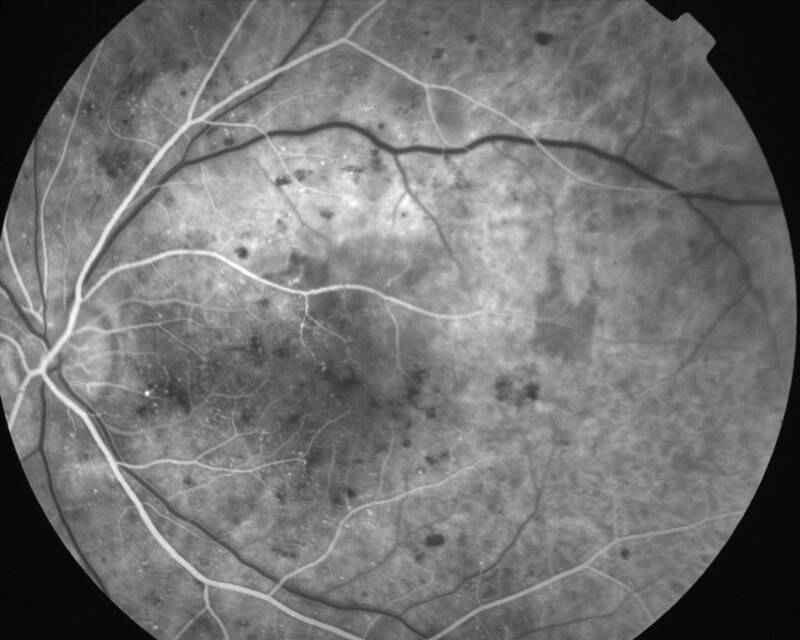

IMG0004.JPG